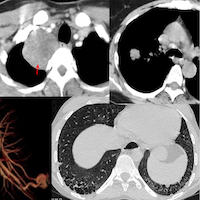

COD 149 - The Subtle Lung Signs that Confirm Sarcoidosis

40-years old with fever, weight loss, raised creatinine.

A left supraclavicular node biopsy before the CT scan showed non-caseating granulomatous disease with GeneXpert negative for TB.

The video discusses the case, the differential of bilateral hilar adenopathy and then why evaluating the lungs in detail can help us pick up subtle signs of disease that can help clinch a diagnosis of sarcoidosis as in this case or tuberculosis, as the case may be.